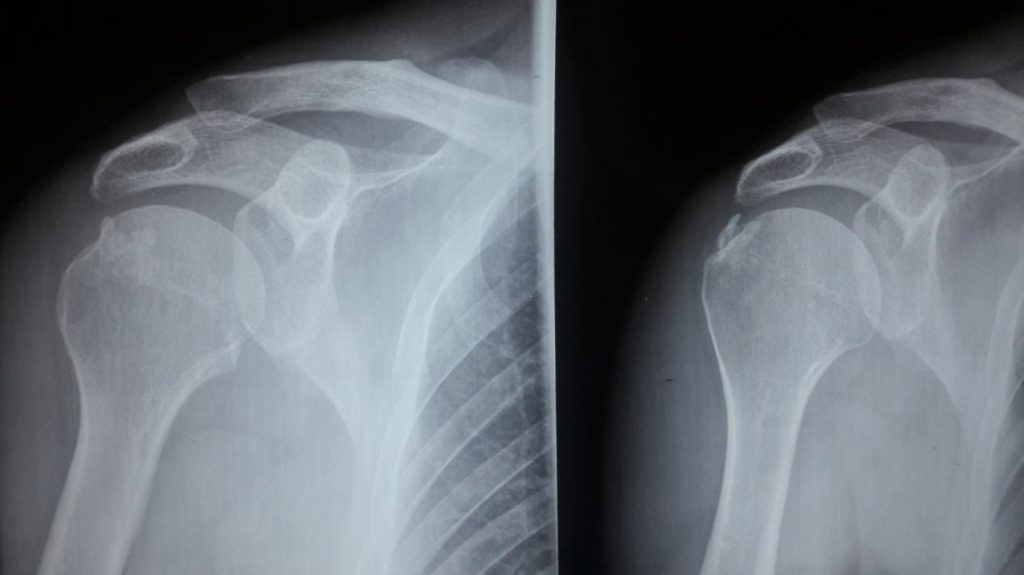

Οι συνηθέστερες απεικονιστικές μέθοδοι για την επιβεβαίωση της ασβεστοποιούς τενοντοπάθειας είναι ο διαγνωστικός υπέρηχος, η απλή ακτινογραφία και η μαγνητική.

Εικόνα 1: Ακτινογραφία-Ασβεστοποιός τενοντοπάθεια ώμου